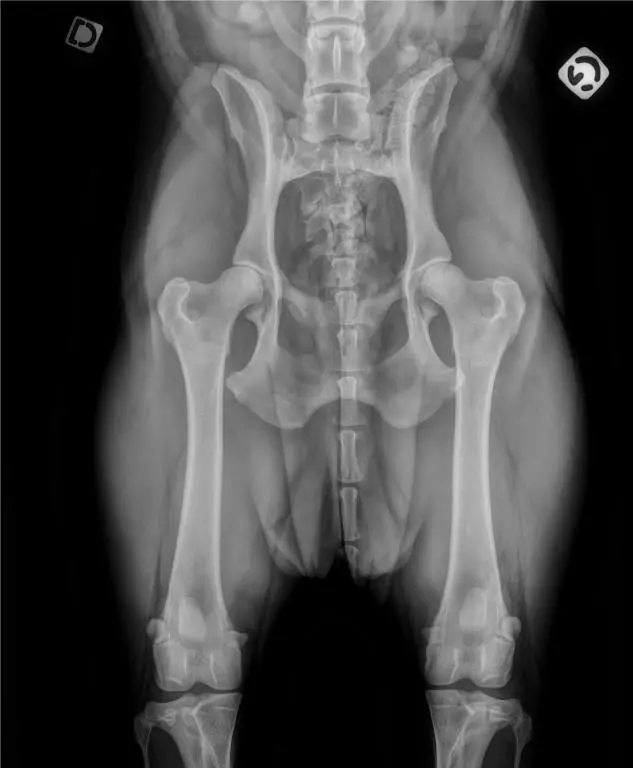

Dysplasie : B cardiopathie : Aso-Pso |